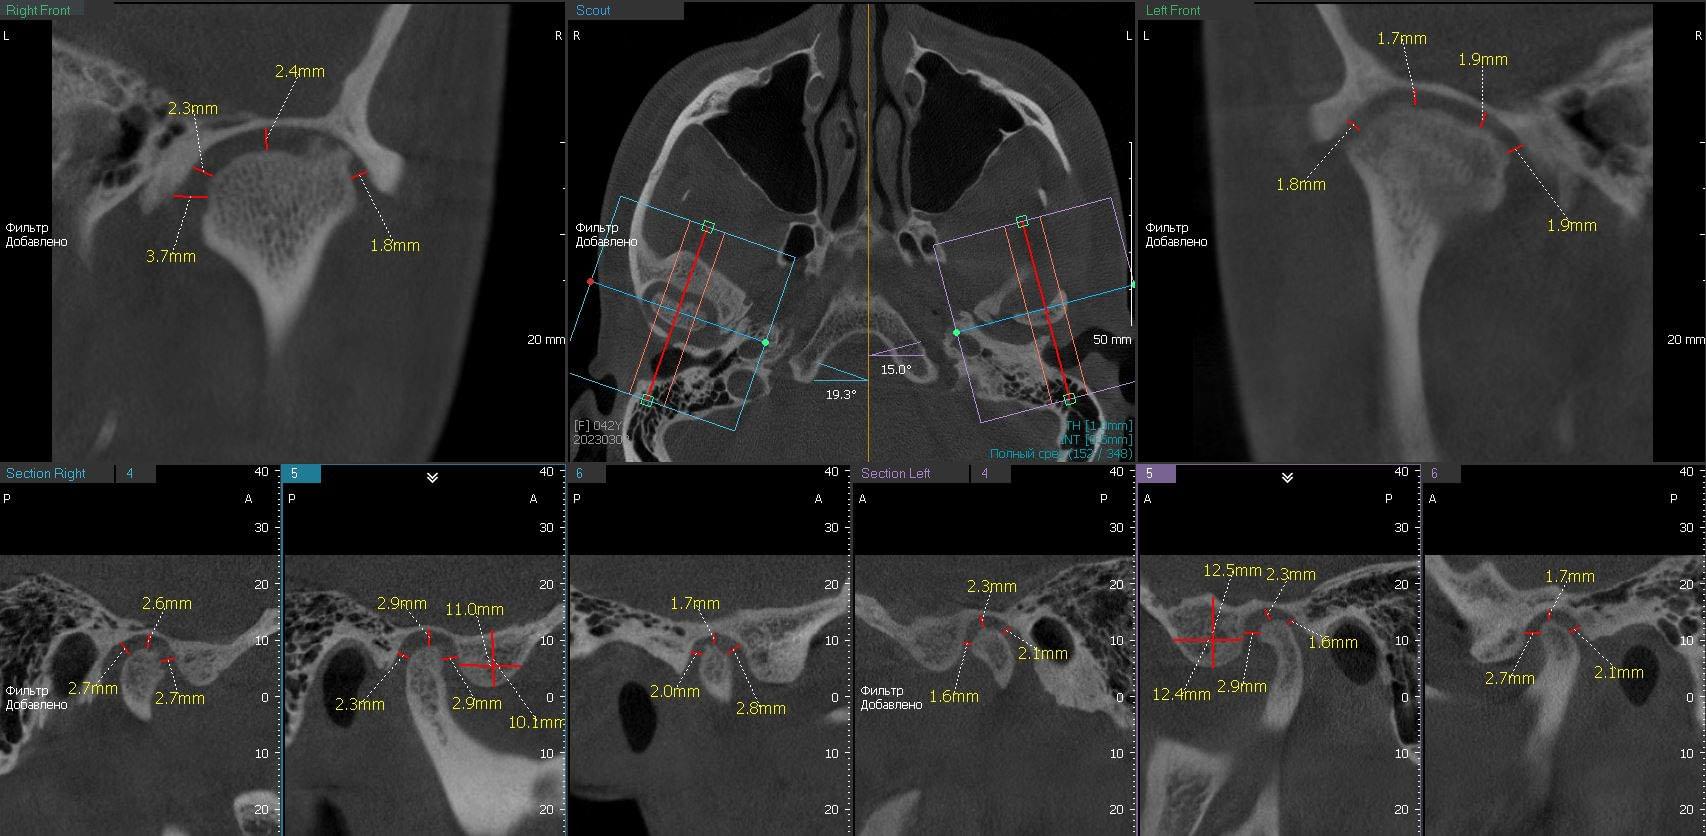

Pokud máte pochybnosti o svém temporomandibulárním kloubu, Myray Lab je tvoje spolehlivý Partner v diagnostice a identifikaci příčin této dysfunkce.Specializujeme se na provádění CT kloubů, lebek a okolních tkání, které nám umožňují podrobně vyhodnotit struktura a Funkce temporomandibulárního kloubu.

Jednou z hlavních výhod spolupráce s laboratoří je naše vysokoškolské vybavení, které Používá se v procesu CT.Používáme pokročilé technologie, které poskytují obraz vysoký vlastnosti a umožňují vám získat podrobné informace o stavu kloubu.Naše společnost Myray Lab použití inovativní metody a přístupy, které pomáhají našim klientům při přesné diagnóze a porozumění Problémy o jejich temporomandibulárním kloubu.

Zdraví našich zákazníků je naší prioritou, takže k každému nabízíme individuální přístup Pacient, který nás kontaktuje pro diagnostiku dysfunkce temporomandibulární kloubů.Náš Zkušení odborníci používají kombinaci klinické studie a CT skenování, aby to zjistili Příčiny příznaků a vyvinout účinný léčebný plán.